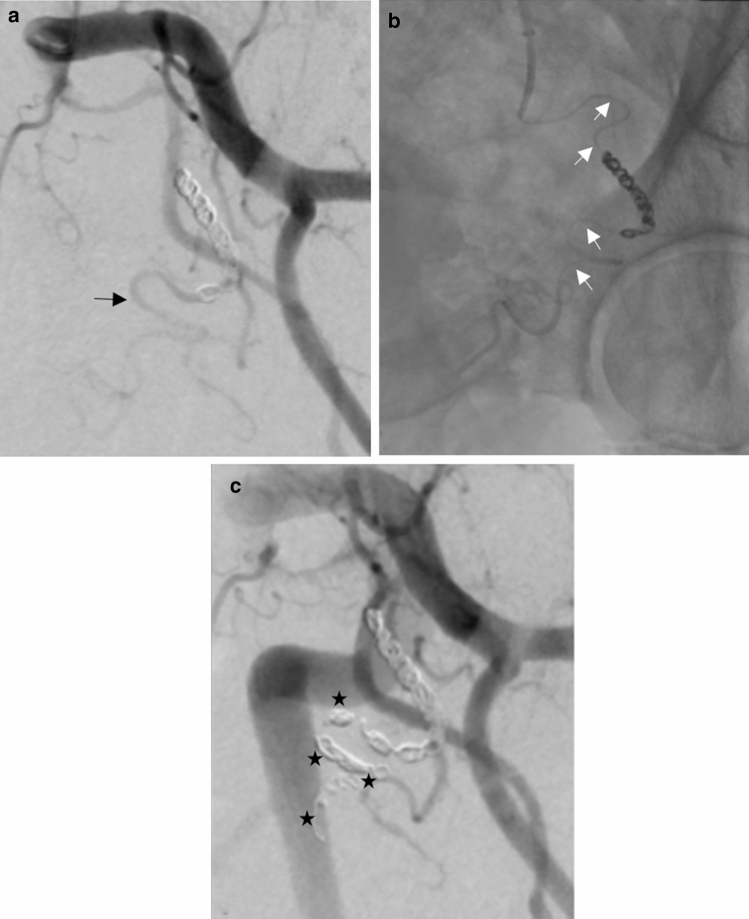

Within the study cohort, repeat PAE was performed for two patients. In a patient with recurrent hematuria, repeat PAE at two months demonstrated that the left PA coil pack was non-occlusive. Technical success was achieved with catheterization of the PA distal to previous coil embolization (Fig. 2) with resolution of hematuria. In another patient with persistent nocturia, repeat PAE at five months demonstrated prostate revascularization was via the left pudendal artery and right posterior-lateral PA branch without recanalization of the main PAs.

Fig. 2.

77-year-old male status post PAE with coil embolization of the PAs with recurrent hematuria presenting for repeat PAE a Digital subtraction angiogram of the left PA demonstrating persistent antegrade flow in the PA distal to the coil pack (black arrow) b Catheterization of the PA distal to the existing coil pack with a microcatheter (white arrows) c Digital subtraction angiogram of the left PA after additional coil embolization (black stars) without flow through the main PA